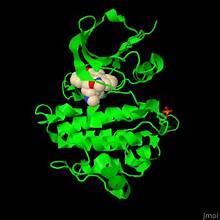

- Общая характеристика эндокринной системы, гормонов. Клетка-мишень: виды рецепторов. Вторые посредники

1.4. КЛАССИФИКАЦИЯ И МЕХАНИЗМ ДЕЙСТВИЯ ГОРМОНОВ

Классификация гормонов. Функции гормонов. Образование, транспорт и метаболизм гормонов. Механизм действия гормонов. Регуляция активности эндокринных желез: гормоны гипофиза и гипоталамуса.